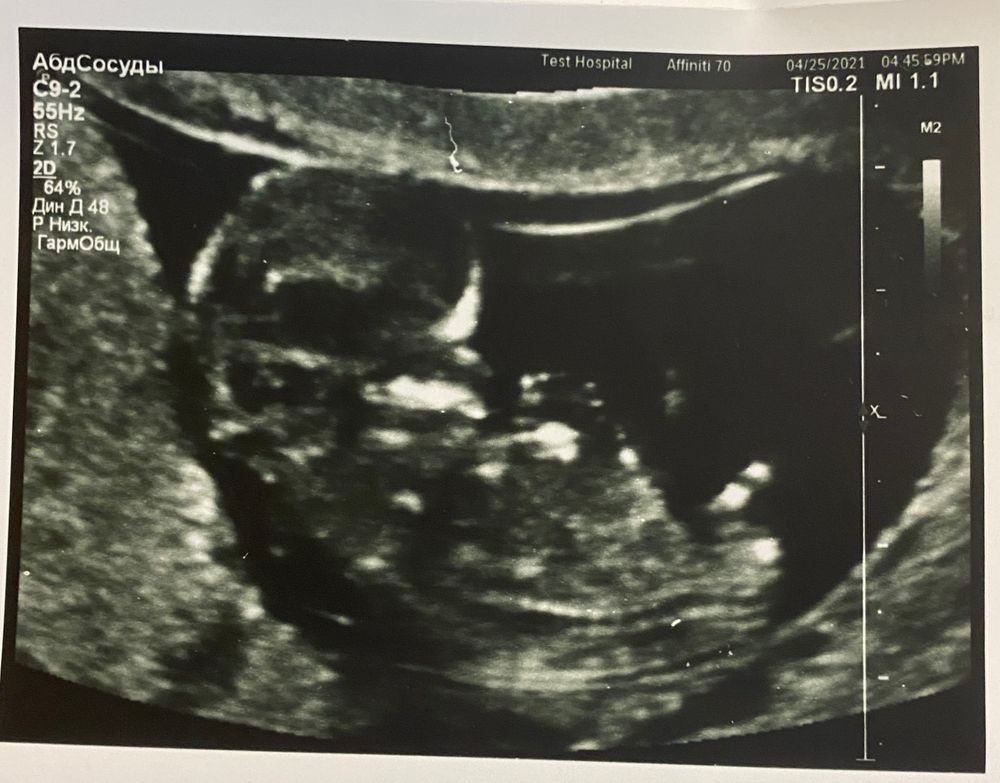

УЗИ, КТГ, доплерВчера был первый скрининг, в этот раз узи до скрининга решила не делать, поэтому с таким нетерпением ждала этого дня! Акушерский срок - 11.5, по УЗИ чуточку опережаем - 12.1. Малышок уже настоящий человек, врач показала ручки, ножки, ушки, все рассмотрели в деталях. Так трогательно 😍 малыш активно шевелился, а потом стал сосать большой пальчик, блин - я чуть не расплакалась там от счастья )))

КТР 54, ЧСС 158. Все в норме, все хорошо и это главное 😇

А дальше узист сказала, что это на 100% мальчик 🙈😁 что между ножек явно формируется писюн (на фотке ниже в самом центре) вот что то я сомневаюсь, неужели на таком сроке можно так точно определить? (Не по углу наклона, а просто по внешнему виду?) Как думаете?